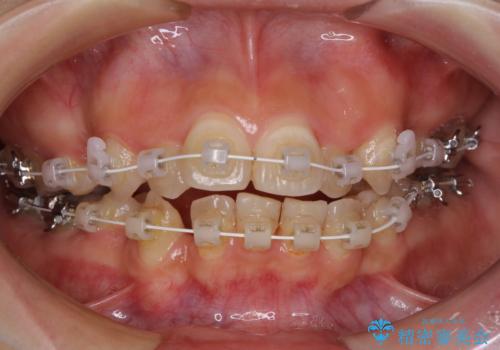

- 矯正装置

- 審美装置

上顎の左右側切歯(前から2番目)が裏側に隠れいてる状態で、咬み合わせや清掃性に大きな問題が認められました。

叢生が著しいため、左下以外の第一小臼歯3本を抜去し、目立たないワイヤー装置にて矯正治療を行うこととしました。

これほど顕著に裏側に隠れいてる歯ですと、仕上がったときに両隣の歯と軸に差が認められることが多いのですが、殆ど違和感のない歯並びを達成することができました。